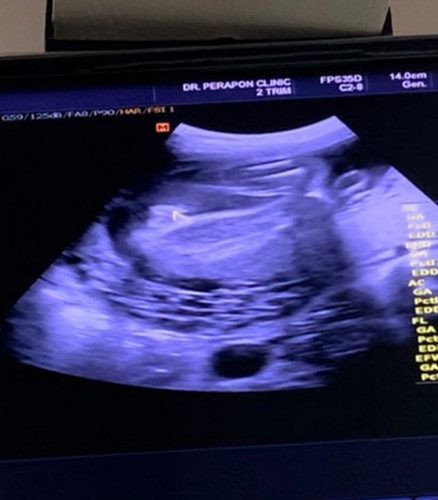

อยากทราบว่าเเบบนี้น้องเป็น ผู้หญิงหรือผู้ชายคะ 26weekค่ะ ขอบคุณค่ะ💗

ผู้หญิงจ้า